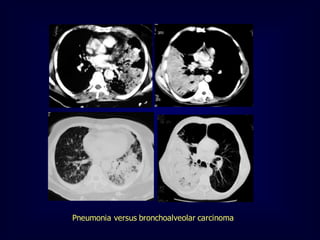

Bronchoalveolar carcinoma Other causes:Lymphoma, pulmonary edema, some types of pneumonia [obstructive, lipoid] 6-10% of primary lung cancer Cough, sputum, weight loss, hemoptysis, bronchorrhea Radiographic patterns : Single or multiple pulmonary nodules [ Air bronchogram] Segmental or lobar consolidation. Diffuse air space disease . CT angiogram (non specific) Visualization of pulmonary vessels within airless lung

• 75.

• 76.

• 77.

• 78.